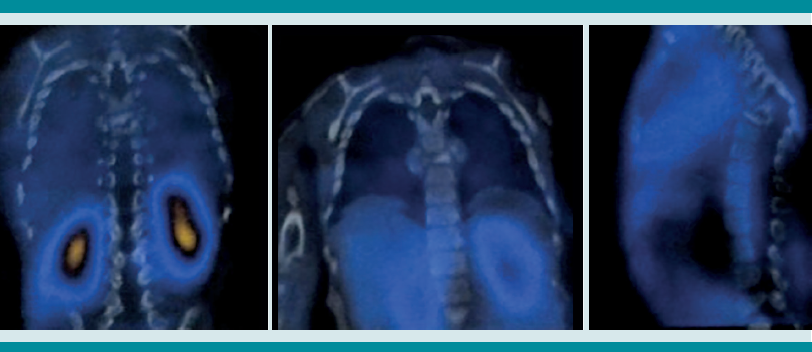

Estudios de imagen

La tomografía axial computada de alta resolución puede demostrar lesiones de la primoinfección o linfadenopatía, aun cuando la radiografía de tórax se reporte normal.13 La resonancia magnética se utiliza en mayor medida para la tuberculosis músculo esquelética y de tejidos blandos y, como en este caso, para diferenciar una tumoración de un granuloma en la columna vertebral.14 Otros métodos, como la gammagrafía, que con marcadores como Tecnecio 99 tiene una especificidad de 30% y con galio de 70%. El SPECT y PET tienen mejor especificidad que la tomografía o gammagrafía para discernir entre tuberculosis y lesiones cancerosas,15 con un valor predictivo negativo mayor de 90%, a diferencia de pacientes con tuberculosis pulmonar, además de mayor captación e identificación de lesiones óseas se puede utilizar como auxiliar en tuberculosis extrapulmonar. Finalmente, pueden ser de gran ayuda para determinar el grado de actividad de la enfermedad y la respuesta al tratamiento indicado.